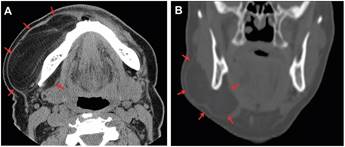

Inicialmente se solicitó una Tomografía Computada (TC) con medio de contraste y exámenes de laboratorio (perfil hematológico, VHS, electrolitos séricos, glucosa y perfil de la coagulación) cuyos hallazgos fueron normales. En la TC se observó un aumento de volumen hipodenso, bien delimitado, encapsulado, que abarcaba región geniana, maseterina y cervical alta. Además, en la exploración de la TC de observó una extensión de la lesión a piso de boca (Figura 2).

Figura 2. Tomografía Computada (TC) con medio de contraste. Cortes axial (A) y coronal (B) de cabeza y cuello donde se observan límites y extensión de la lesión tumoral (flechas)